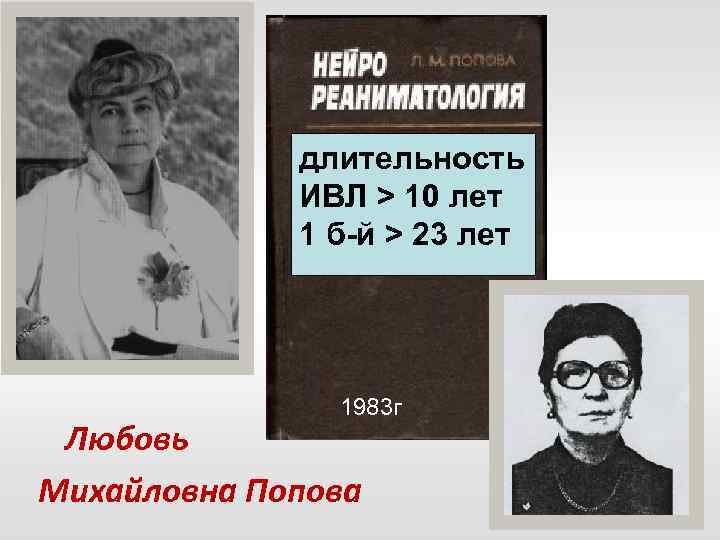

длительность ИВЛ > 10 лет 1 б-й > 23 лет 1983 г Любовь Михайловна Попова

длительность ИВЛ > 10 лет 1 б-й > 23 лет 1983 г Любовь Михайловна Попова